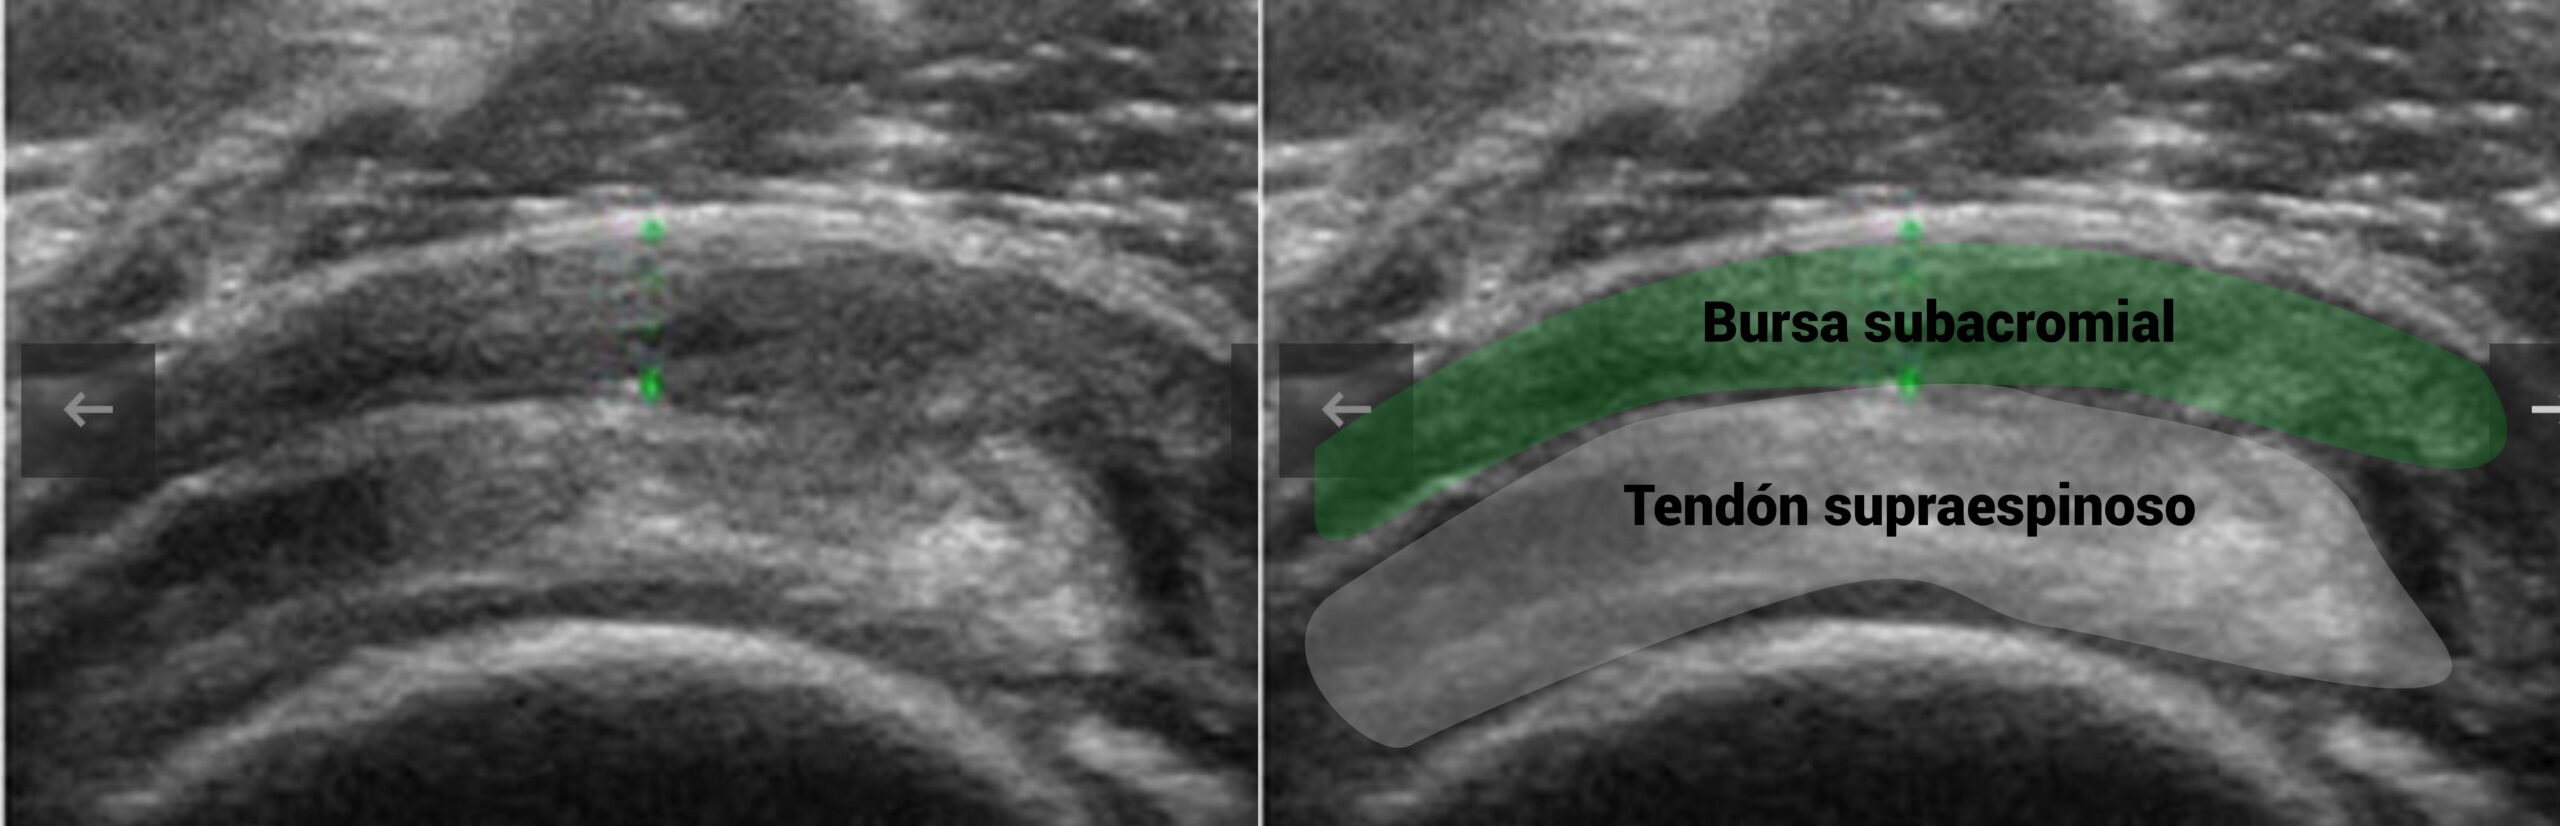

La exploración física y la ecografía, nos orientaron a pensar en un dolor subacromial, problabemente relacionado con el manguito.

La imagen ecográfica de este paciente se ve así:

Dolor en región deltoidea, percibido como difuso, con arco doloroso y molestias nocturnas en fases irritativas. Si la eco muestra bursa sensibilizada o tendón reactivo y el paciente no tolera la progresión de cargas, el PENS puede ser un gran aliado.

Estimulación eléctrica percutánea para bursitis subacromial

Dolor de carácter inflamatorio, presente por la noche o en reposo, que empeora con gestos repetidos por encima de la cabeza. El PENS puede bajar la reactividad, tanto para realizar un programa de ejercicio terapéutico, como en el día a día del paciente.